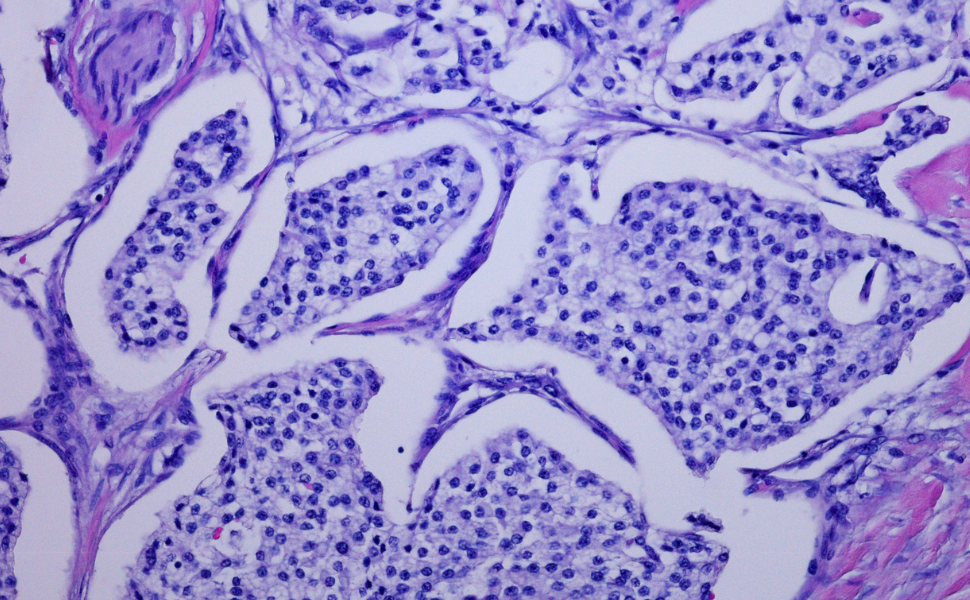

Tumori neuroendocrini

Neoplasie che originano dalle cellule del sistema neuroendocrino, capaci di produrre ormoni; richiedono un approccio diagnostico e terapeutico specializzato.